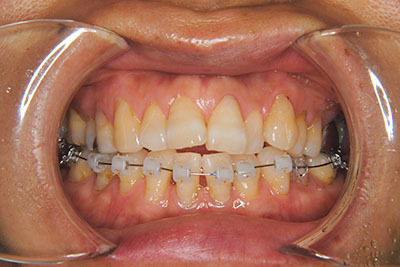

おとなの方でも矯正治療をあきらめないでください!

いくら歯が動き易くとも、本人がやる気でなければ効果は出ませんし、むし歯発生のリスクも高まります。おとなの方は顎の成長が終わっているため、治療の計画が立てやすいとも言えます。「もう大人だから…」とあきらめず、一度ご相談ください。